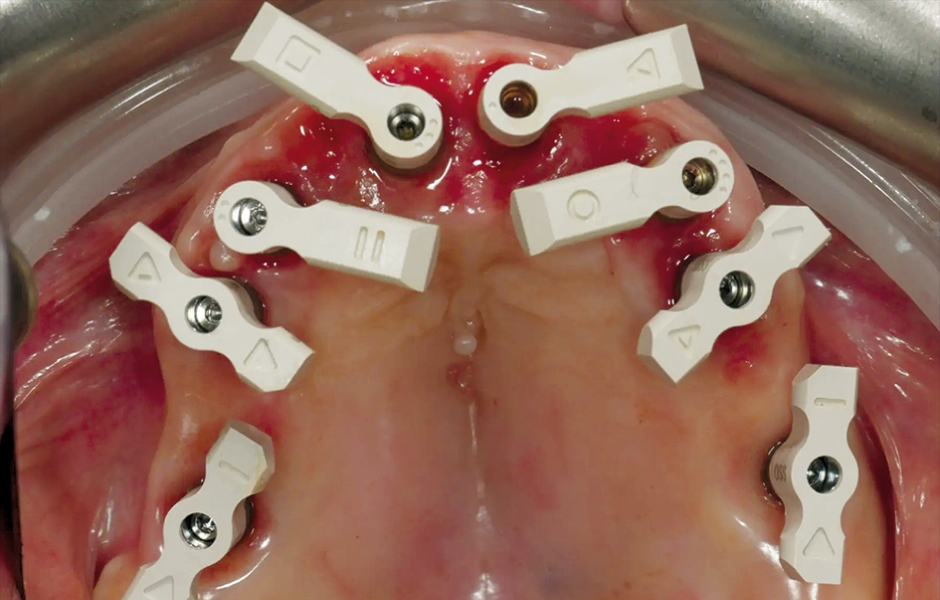

V den operace byla aplikována lokální anestezie a první chirurgická šablona byla stabilizována na zbývajících zubech k přípravě pěti fixačních pinů. Poškozené zuby byly extrahovány a druhá chirurgická šablona byla upevněna v připravených místech. Osm implantátů (Osstem TSIII SOI, Osstem Implant) bylo umístěno – pět do čerstvých extrakčních alveolů a tři do dříve zahojených oblastí. Všechny implantace proběhly plně navigovaně pomocí chirurgické šablony bez kovových pouzder a s dedikovanou chirurgickou sadou (OneGuide KIT, Osstem Implant; obr. 8). [11] Jeden implantát vyžadoval krestální sinus lift, který byl proveden plně navigovaným přístupem (OneCAS KIT, Osstem Implant; obr. 9). Xenogenní kostní materiál (A-Oss, Osstem Implant) byl použit k vyplnění extrakčních alveolů a dutiny sinu. [12] Na všechny implantáty byly okamžitě nasazeny multi-unit abutmenty a dočasné abutmenty (Osstem Implant) podle konceptu „one abutment, one time“. [13] Předem připravená dočasná protetika na bázi PMMA s kovovou výztuhou byla vložena a ihned fixována v ústech. V ordinaci byly provedeny úpravy pro dosažení správné okluze (obr. 10–12). Pacient obdržel pooperační instrukce a medikaci.

Obr. 13: Scan body SmartFlag nasazené pro intraorální otisk.